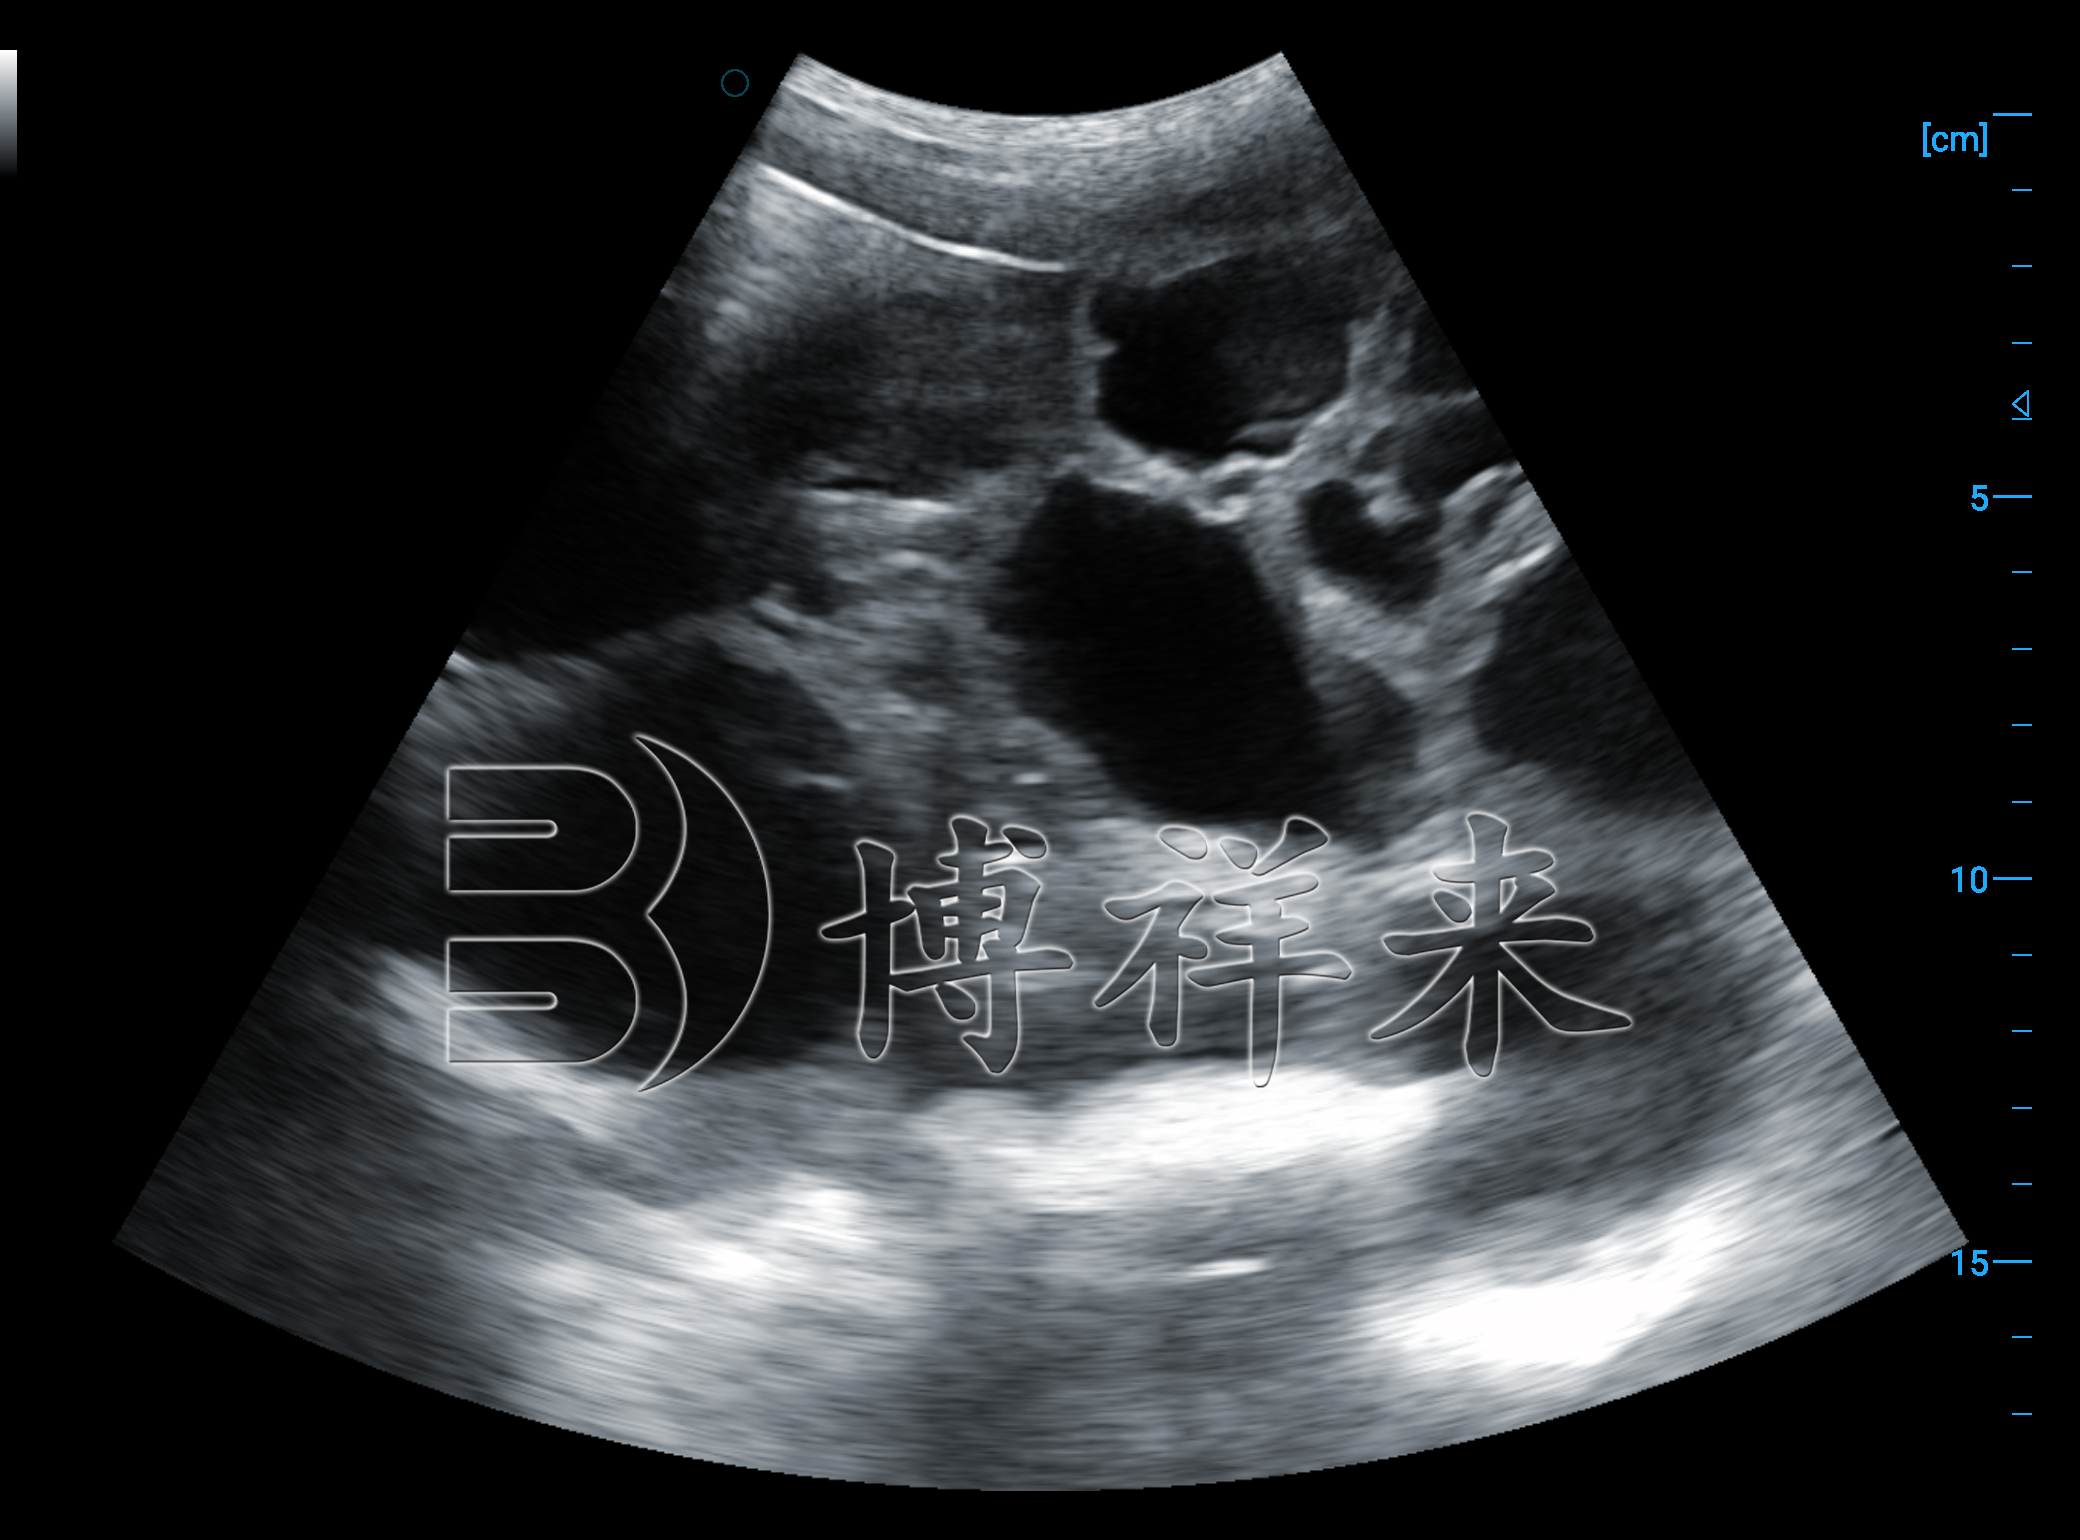

在使用 猪用B超机测胎仔数 时,图像中的胎体多呈点状或小圆形亮区,随着胎龄增长,胎头骨骼回声增强,轮廓愈发清晰。操作员沿子宫方向扫查时,会依次看到多个胎体“排队”般排列,不同胎体之间具有相对独立的羊膜腔和活动空间。

经验丰富的技术员通常会从左腹到右腹、从前向后反复扫查,确保不漏掉胎体。由于母猪的子宫较长且胎仔分布较分散,扫查完整性非常关键,这也是为什么 图像清晰度高的猪用B超机 能显著提高胎仔数判断准确度的原因。